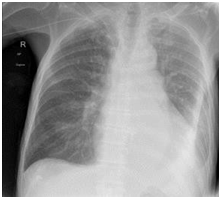

Fig 1 – Computed Tomography scan of the chest, abdomen and pelvis: severe relatively concentrical thickening of most of the oesophagus, especially of the oesophageal wall over approx- imately 15.5 cm in length